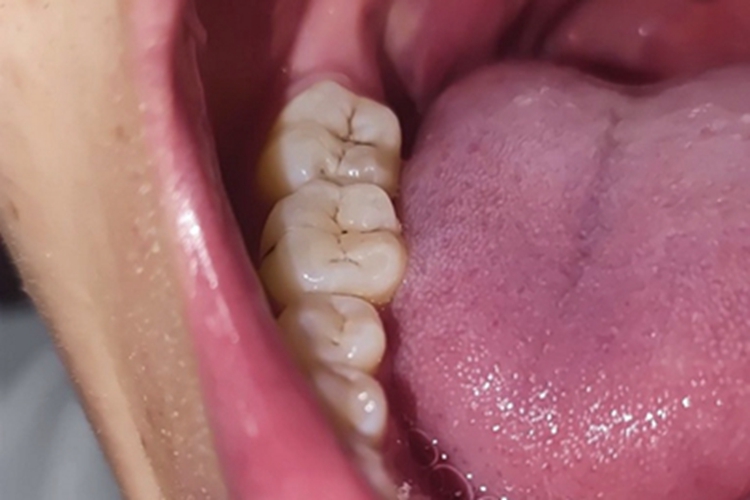

浅龋患者牙齿的窝沟可出现黑色斑纹,呈点状、线状,表面没有光泽,随着疾病发展,最终呈片状,并且出现组织缺损,多无龋洞形成,患者一般无自觉症状,对冷、热、酸、甜刺激无反应。